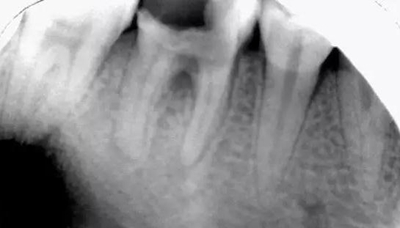

初診時X光片:根分歧炎癥懷疑有底穿,和患者交待病情和費用后開始治療。

初尖銼,根測儀測量長度后拍照

初尖銼X光片:現(xiàn)在根測儀的準(zhǔn)確性的卻非常之高。